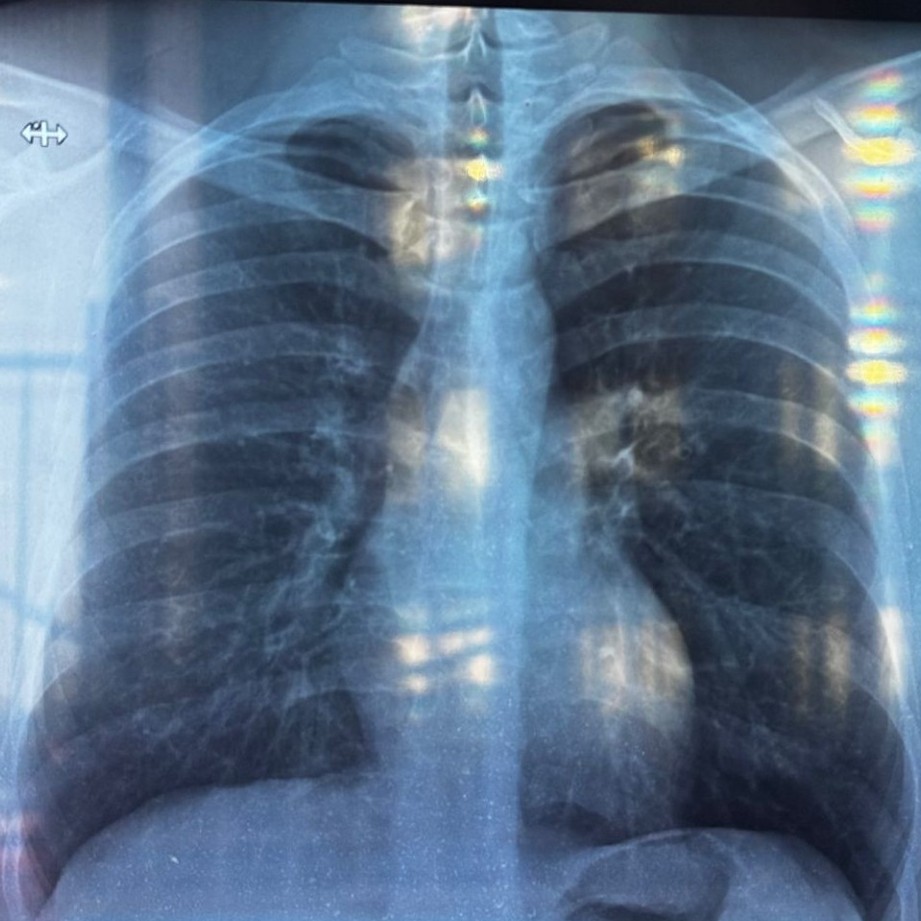

Однако, я могу описать некоторые общие наблюдения, которые видны на представленном рентгеновском снимке грудной клетки:

* На снимке видны легкие, сердце, ребра и часть позвоночника.

* Легочные поля выглядят относительно прозрачными, что является нормой.

* Прослеживается легочный рисунок, который может быть усилен в некоторых областях.

* Контуры диафрагмы четкие.

* Сердце имеет нормальные размеры и форму.

* Костные структуры (ребра, ключицы) без видимых патологических изменений.

Для точной интерпретации и постановки диагноза требуется профессиональная медицинская оценка.